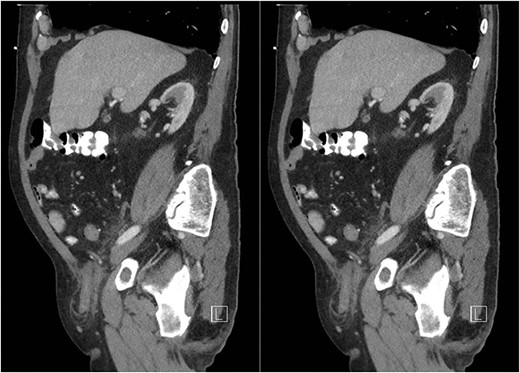

An 81-year-old male with a past medical history of childhood repair of cardiac septal defect presented to our emergency department (ED) with a two-day history of vague abdominal pain that migrated to his right groin with an associated non-reducible right groin mass. The non-reducible groin mass persisted, and his pain progressed that prompted him to come to the ED. Clinical examination revealed a firm, tender and irreducible right inguinal mass. The remaining clinical and laboratory tests were normal. Contrast-enhanced computed tomography (CT) of the abdomen and pelvis was performed. CT presented an acute appendicitis within a right inguinal hernia and a dilated appendix, measuring 13 mm in diameter and demonstrated periappendiceal fat stranding with no evidence of rupture (Figs 1–3). Patients’ history, physical exam and imaging findings were consistent with the preoperative diagnosis of an Amyand’s hernia with acute appendicitis. It was determined the patient will require operative intervention.

Sagittal CT abdomen with oral contrast showing a dilated appendix periappendiceal fat stranding within a right inguinal hernia and no evidence of rupture.